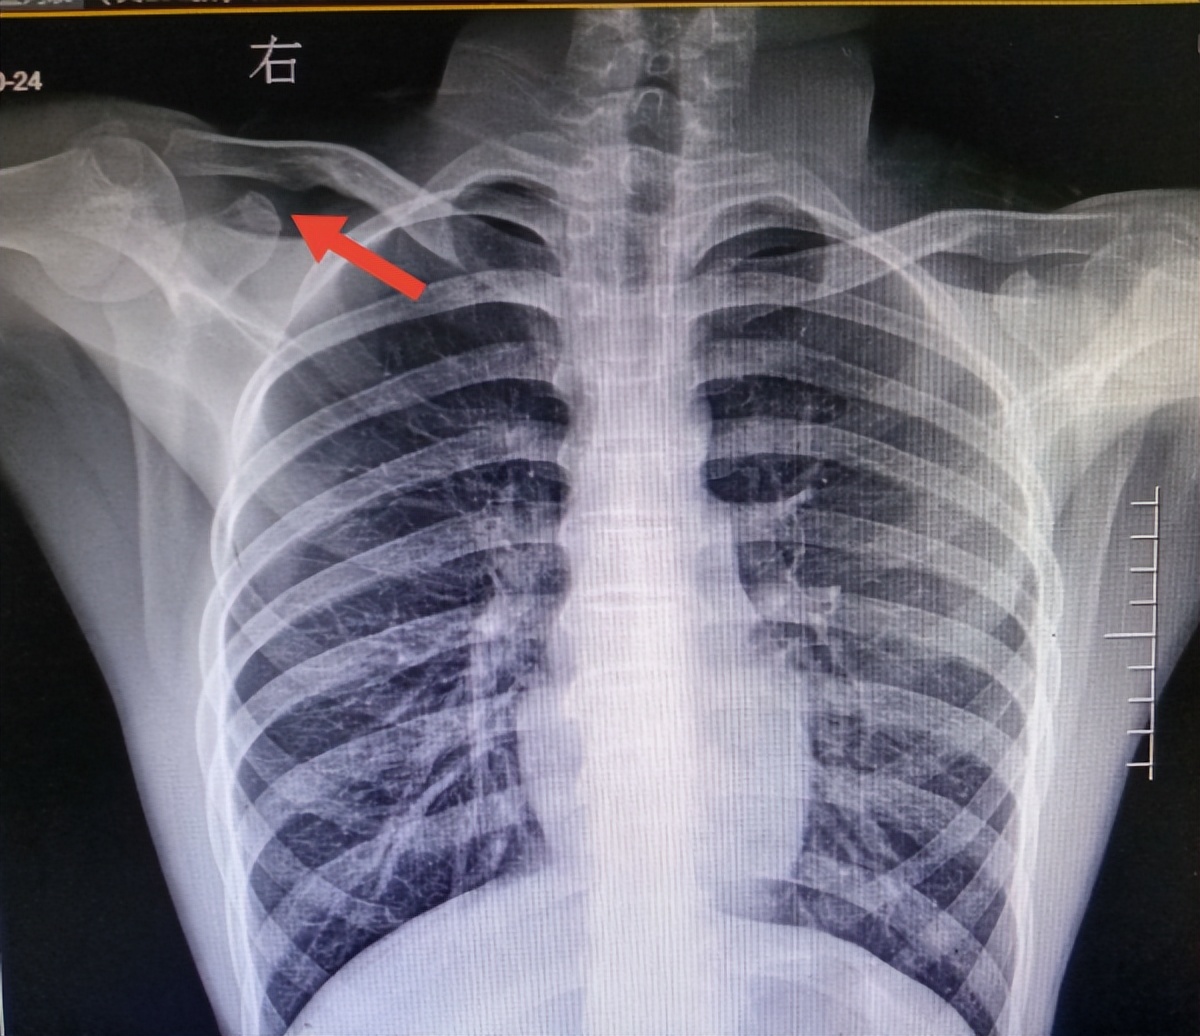

患者在癫痫发作期间,避免大力按压其肢体,需待病人发作缓解、病情平稳后,制动脱位的肩关节,避免肩关节运动,及时去医院就诊。医生进行查体、肩关节前后位X线摄片等相关检查,了解患者肩关节脱位的具体方式,癫痫专科医生给予调整药物治疗,控制癫痫发作,同时请骨科医生会诊,对脱位的肩关节实施紧急手法复位。在此提醒,患者家属不可自行进行脱位关节复位操作。